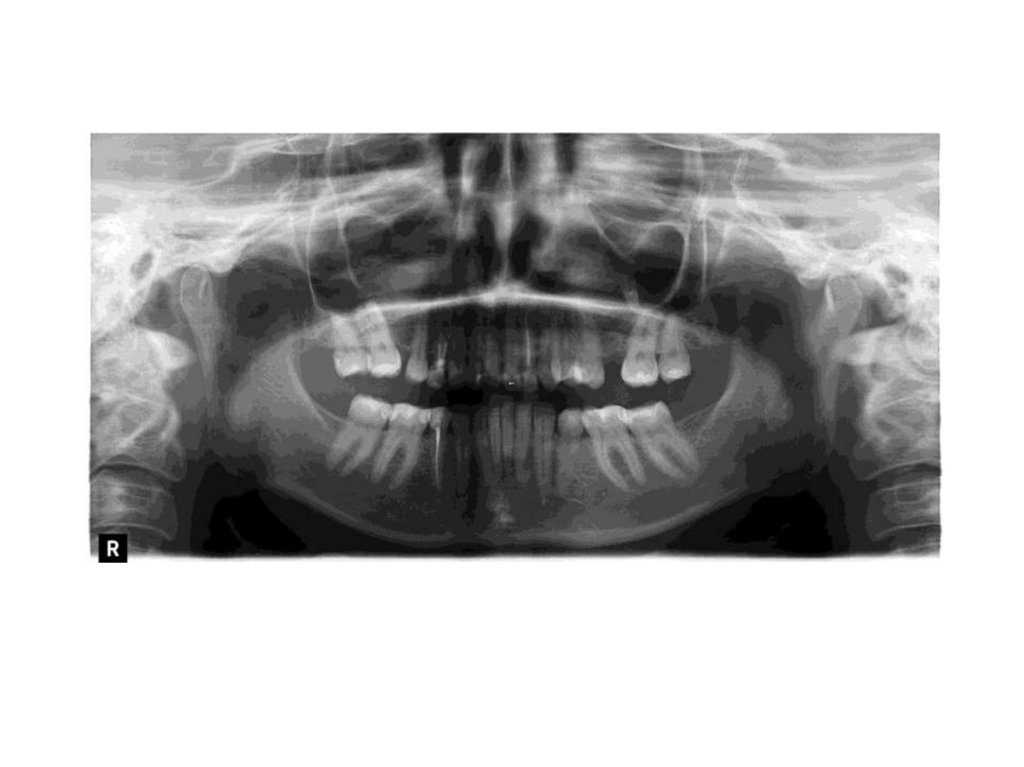

Когай Виктория Валерьевна

25.06.1985 ( 37 лет)

Дата консультации: 02.10.2022

Дата диагностики : слепки 02.10.2022

Снимок КТ 24.06.2022

1.2

Наклоны резцов

1.1

2.1

2.2